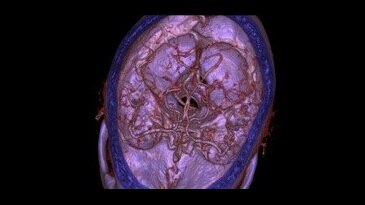

Vasküler Görüntü Galerisi